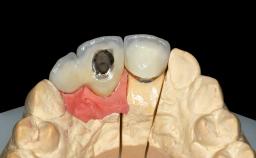

A 38-year-old woman presented with an esthetically unacceptable fixed partial denture replacing teeth 11, 21, 22. She had lost these teeth due to trauma when she was a child. The patient was not in pain but very concerned based on her previous experience that dental treatments had never satisfied her esthetic expectations. She was in good general health and reported no regular medications. No periodontal disease was noted despite the fact that the buccal flange of the prosthesis impeded cleaning of the tooth abutments. The patient did not smoke and complied with home maintenance requirements, as evidenced by her good oral hygiene status.